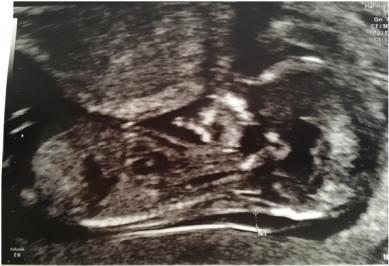

The nub theory?

Attachment 35579